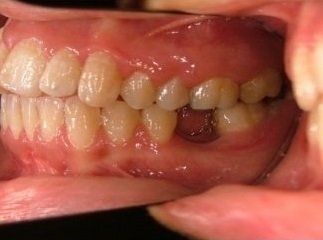

Il trattamento ortodontico non è solo per i bambini: se hai denti storti, affollati, mancanti o prominenti che ti impediscono di masticare e parlare liberamente, potrebbe essere necessario rivolgersi a uno specialista. L’ortodonzia prevede l'uso di apparecchi ortodontici, che possono essere fissi o rimovibili.

I dentisti studiano infatti le anomalie di costituzione, posizione e sviluppo di denti e ossa mascellari, e progettano l’apparecchio mirando al ripristino della corretta funzionalità dell'apparato masticatorio.